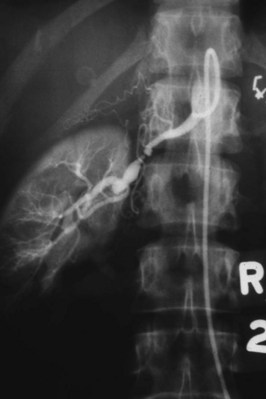

Medial fibroplasia accounts for 75% to 80% of fibrous lesions primarily in women between 25 and 50 years of age. With angiography, arteries demonstrate a “string of beads” in the distal two thirds of the main renal artery and its branches (Fig. 54–43). Multiple microaneurysms can also be appreciated. An estimated 33% demonstrate progression, whereas complete occlusion is rare.

Figure 54–43 Selective right renal angiogram demonstrating medial fibroplasia “beads on a string” in a solitary right kidney.